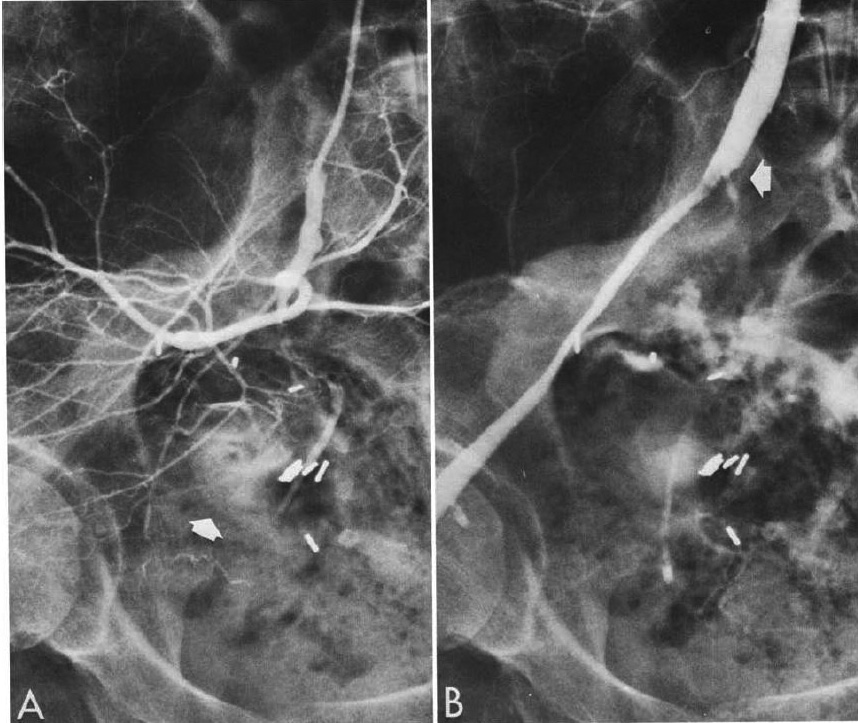

図3.Mallory-Weiss症侯群による出血の治療.(上)左胃動脈造影で,食道噴門移行部の造影剤の血管外漏出が認められる.(下)バソプレッシン投与後.血管が全体に収縮して止血に成功した.

【要旨・解説】IVRによる消化管出血の治療はこの論文を嚆矢とする.著者のBaumはペンシルベニア大学の外科医,Nusbaumは放射線科医で,消化管出血の血管造影診断,経カテーテル的止血法に関する研究の多くは,この2人が先鞭をつけたものである.1963年に,血管造影により消化管出血の診断が可能であることを初めて報告し[→原著論文],1967年には本文中にも引用されているように,動物に様々な血管収縮薬を投与して,作用機序の自律神経系に依存しないバソプレッシンが最も有効であることを示した[16].1968年[17],1969年[15]にそれぞれ少数の臨床例を予備的に報告しているが,本稿ははじめて,48例のまとまった症例数について,その手技と結果を報告している.

48例中28例は,血管造影上出血源不明であるが,門脈圧亢進症に伴う静脈瘤からの出血と考えられた例,8例は血管造影で出血源を同定できたMallory-Weiss症侯群,胃潰瘍などの症例で(図3),いずれもバソプレッシン投与開始数分で出血はとまり,その後数日間持続投与して再発はなかった.この他14例は,門脈体循環シャント術前で,術中の出血低減を目的としたもので,手術が容易になり手術時間が短縮したとしている.

手技は,門脈亢進例では上腸間膜動脈,その他の例は左胃動脈など出血源の血管で,診断造影を行なったカテーテルをそのまま使用してバソプレッシン 0.2単位/mL/分を基本として動注し,止血を確認後,数日間持続投与するとしており,現在行なわれている手技と基本的に同じである.